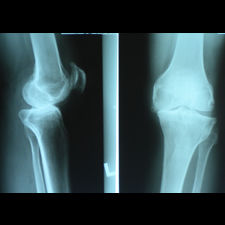

A 58 year old, male patient presented with a history of left knee pain and loss of function over 4 years.

On clinical and radiological examination, he was assessed as having Medial Compartment Osteoarthritis. A uni-compartmental knee replacement was recommended and performed in June 2011. Patient has gone onto complete recovery with a satisfactory clinical outcome. She returned to independent function, six weeks after the surgery and now has an pain-free existence with full function in the right knee after two months.